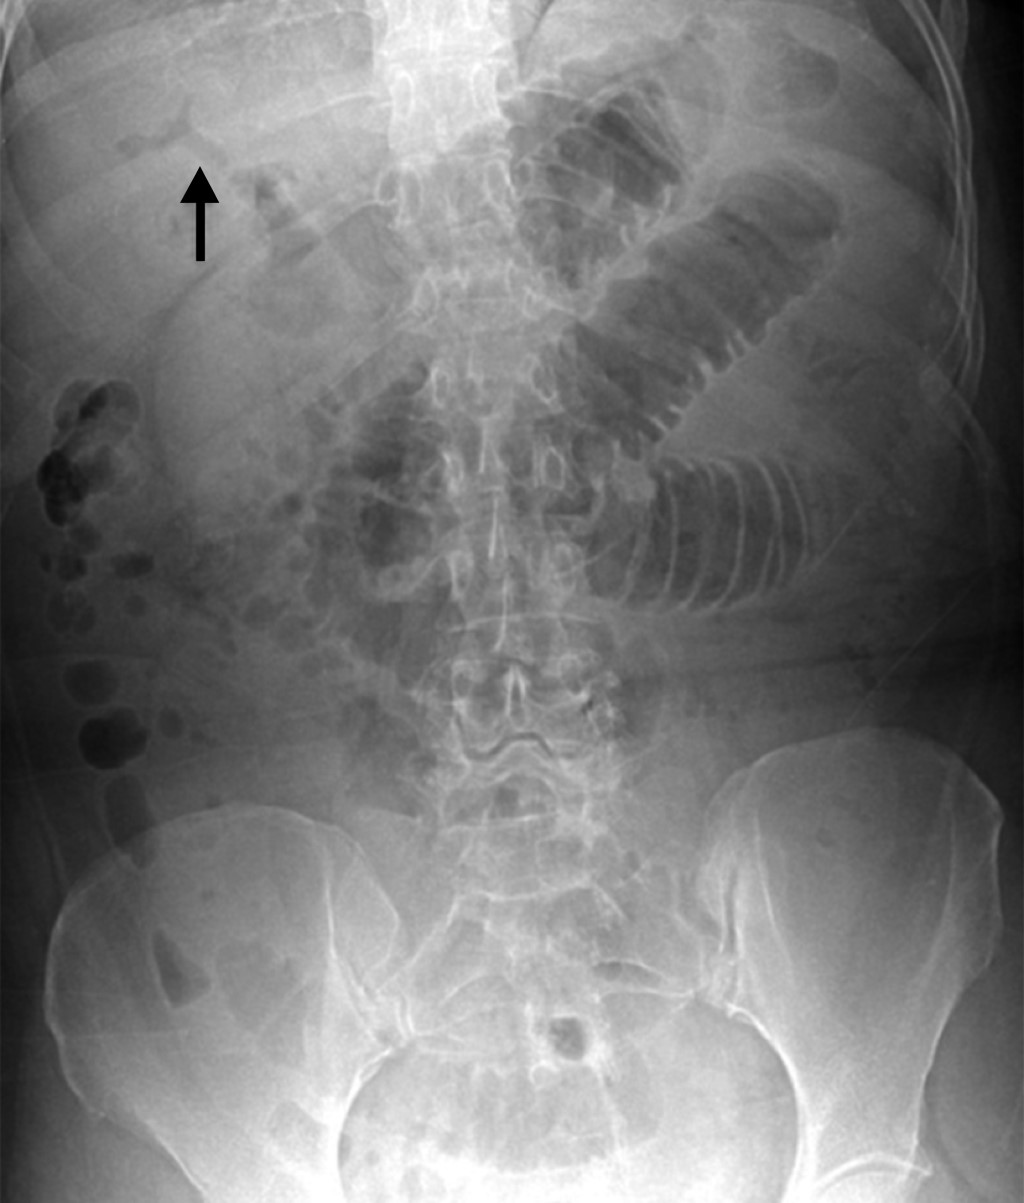

Introduction: Gallstone ileus is a mechanical obstruction of the gastrointestinal tract caused by the impaction of one or more gallbladder stones inside the intestinal lumen through a bilioenteric-fistula. Clinical case: A 59-year-old woman with multiple comorbidities, who went to the emergency room for intestinal obstruction, pneumobilea, and bowel distention is identified by image, so it was decided to enter the operating room for a probable biliary ileus and perform diagnostic laparoscopy, finding a 3.5 cm diameter lithium located in the terminal ileum. Conclusion: Gallstone ileus is a rare complication of cholelithiasis. The treatment integrates rehydration and a surgical approach to correct the cause of intestinal obstruction.

Figure 2